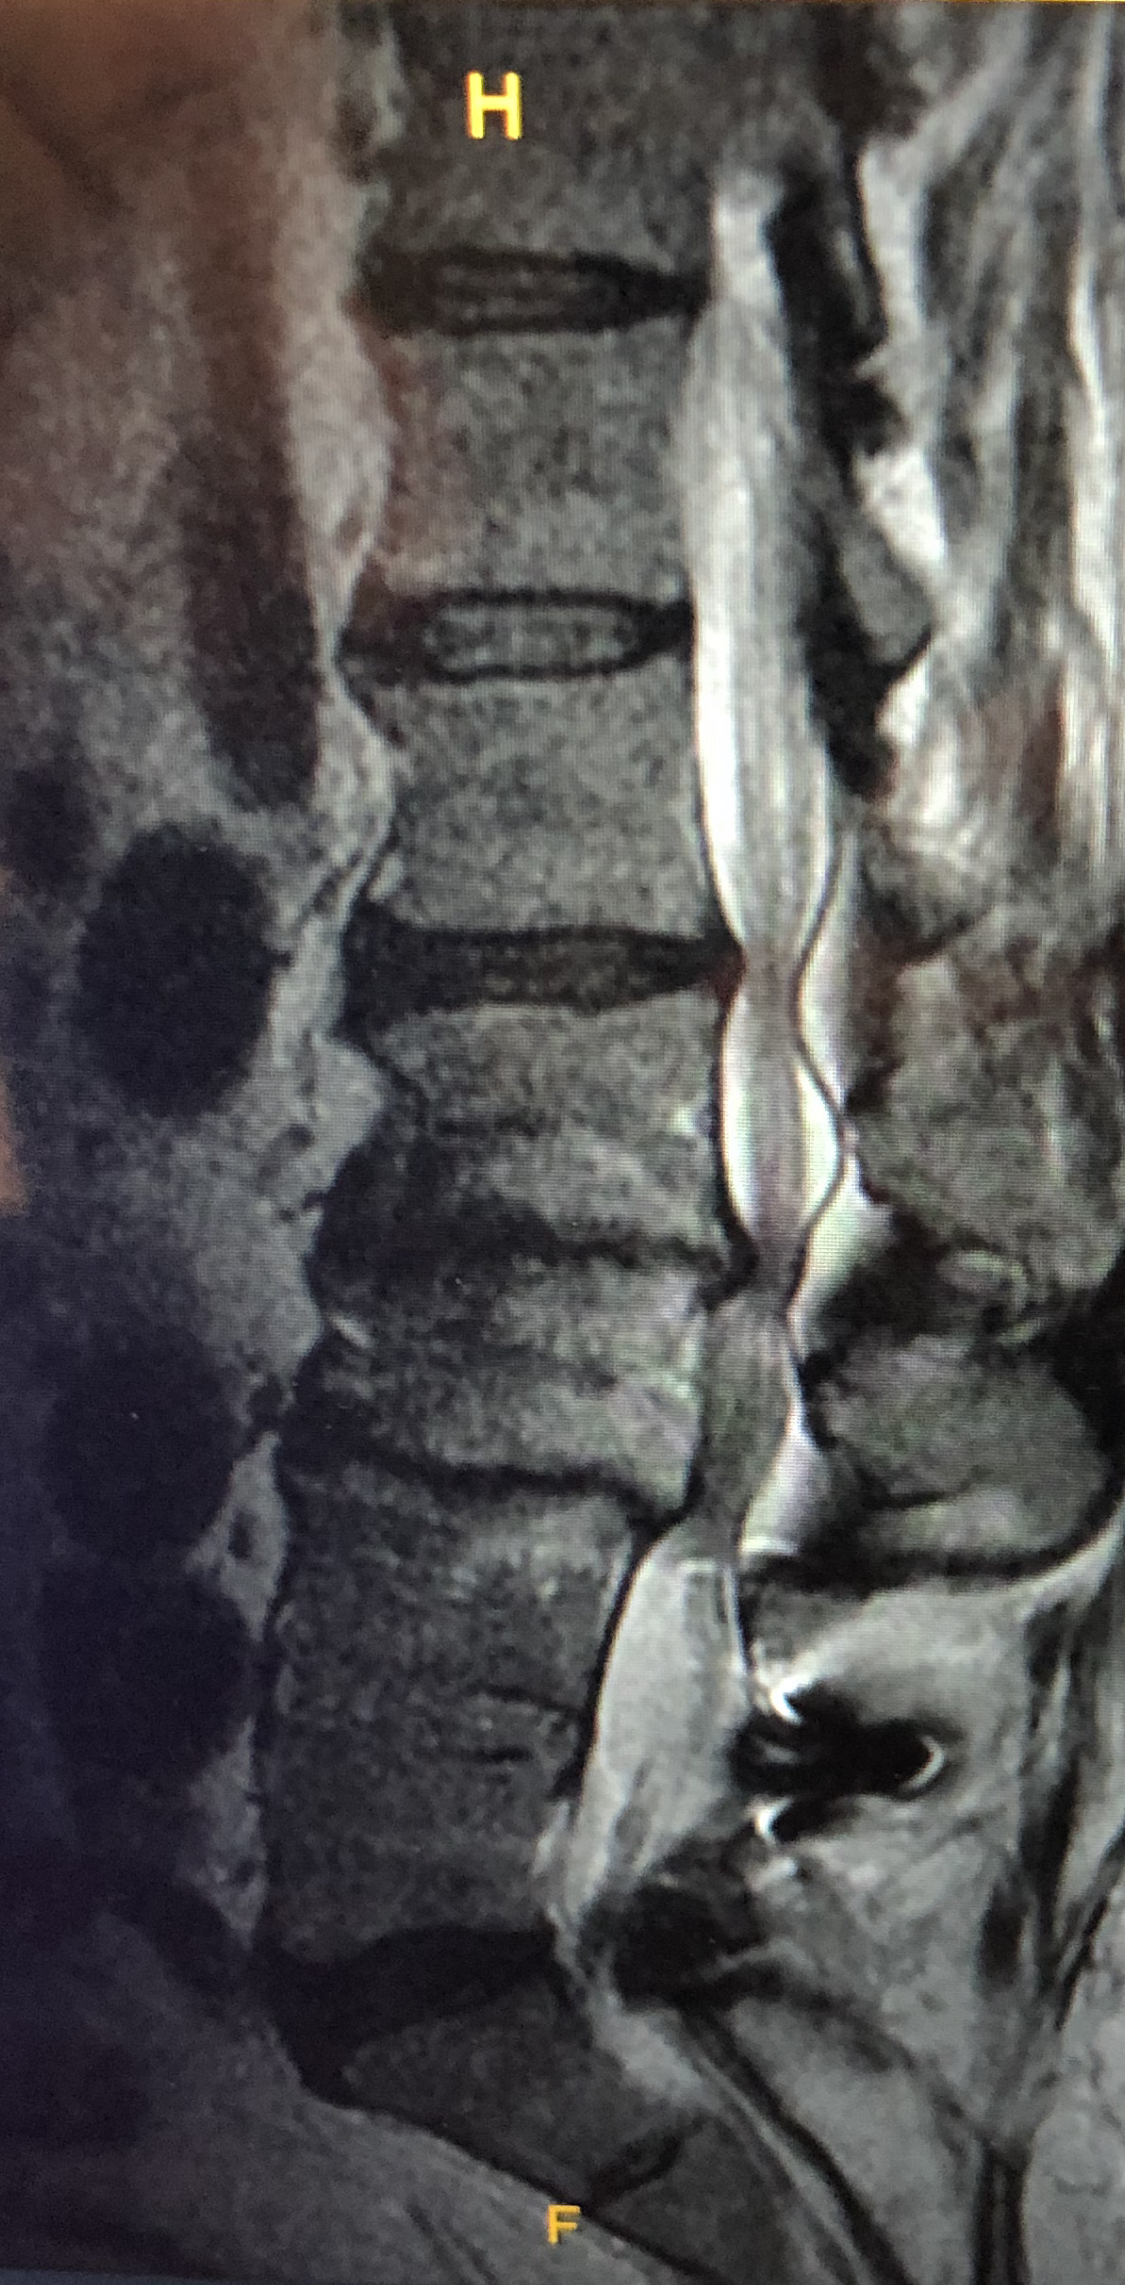

Most of you are probably aware on some level that I’ve had a complaint of back problems for many years. A fusion/discectomy at L4/L5 in 2004 helped a lot, but not 100%. Over the intervening years, my back began again to degrade significantly. Below is an MRI image of my lower spine, taken a little over 3 years ago. We tried a number of mattresses over the years, including a memory foam mattress that didn’t hold up as long as it was supposed to. The next mattress purchase was a split California King Sleep Number bed with one of their higher end mattress sets, and the ability to raise/lower the head and foot of the bed independently for each mattress. It was reasonably comfortable at first, but over time it too began to break down, lose its shape a bit, and resulted in increasing levels of back pain. Then in about 2016 or so, we bought a split California King TempurPedic with the same mechanical traits as the Sleep Number bed. 7 years later, this bed is as comfortable and sound as it was the day we bought it.

FYI, this image doesn’t show my T-spine, which is in almost as bad a shape as my L-spine.